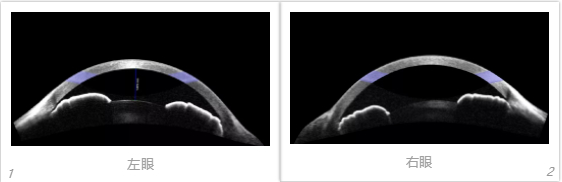

右眼视力:0.15,+6.50DS/-2.25DC×165 右眼晶体混浊C1N2P2,中心凹反光未见。左眼视力:0.04,+9.25DS/-1.50DC×10,左眼晶体混浊C1N2P2,中心凹反光未见。右眼眼轴:17.44mm;左眼眼轴:17.33mm。双眼OCT示:双眼黄斑厚度变薄,视网膜神经上皮层结构也变得模糊。